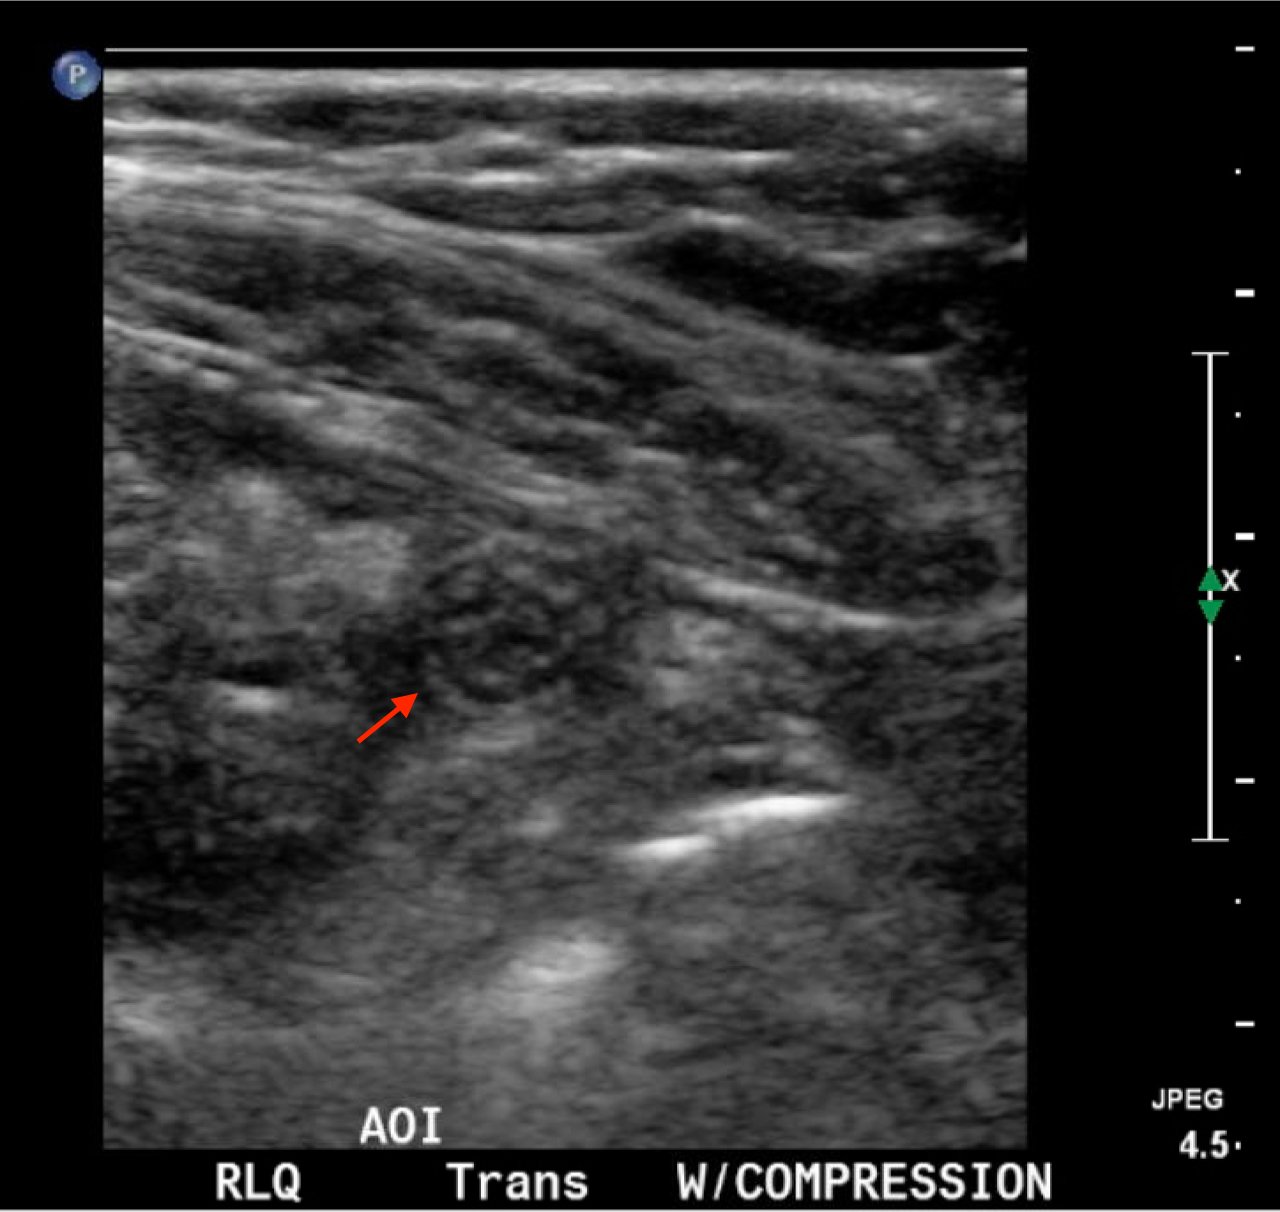

In the long axis video, the appendix appears as an enlarged, non-compressible, blind-ending tubular structure (white arrow) with distinct appendiceal wall layers and lack of peristalsis. In the short axis video, the appendix appears as a target sign (yellow arrow) between the abdominal and psoas muscles. The maximal outer diameter (MOD) measures 11.8mm and the appendix wall measures 0.17mm. There is trace adjacent free fluid and echogenic periappendiceal fat. Transverse axis video and image (red arrow) demonstrate that the appendix is not compressible. These findings are consistent with acute appendicitis.